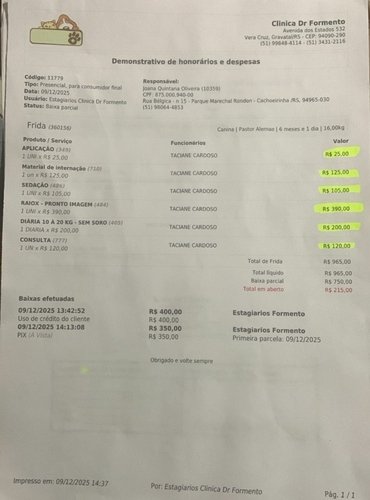

A cirurgia custa R$ 3.900,00, sem contar medicação, soro e outros itens que não entrarão no orçamento.